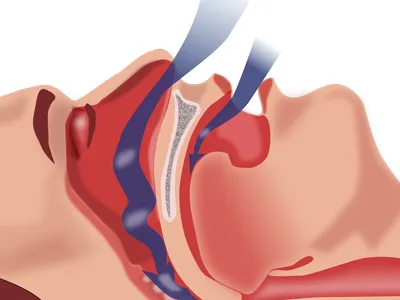

Obstructive Sleep Apnea happens when your breathing is interrupted during slumber. It gets arrested and resumes again repeatedly during sleep. Sleep apnea in Cary is caused by airway blockage that occurs when the throat's soft tissue collapses during sleeping.

Sleep apnea is an obstructive disorder that causes the throat tissue to collapse repeatedly and block the airway while sleeping. The obstructions cause the person to snore. These obstructions typically last for a minute and may occur several times during the night.

Sleep apnea is a condition where the patient suffers from breathing during sleep. As a result, the patient wakes up frequently to start breathing again. This stops the patient from getting sufficient sleep. Obstructive sleep apnea

If you suffer from Obstructive Sleep Apnea in the Cary/Raleigh, NC area we can help. Sleep apnea is a blockage of the airway during sleep that interrupts breathing. Many patients are unaware they even have sleep apnea until someone else tells them that they are snoring heavily, one of the tell-tale signs of the disorder.